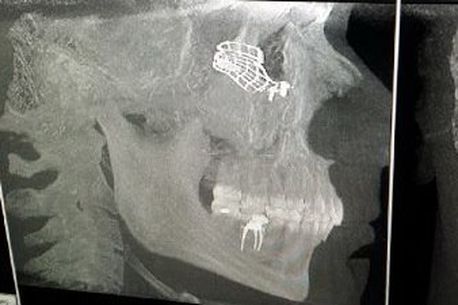

Steaua a publicat, de asemenea, și radiografiile făcute zonei în care Raul Rusescu a fost accidentat de Gabi Mureșan. Se poate oberva prezența unei plăci de titan în zona craniului. Atacantul Stelei a avut probleme serioase și a fost operat la ochiul drept. Rusescu are șanse mici să mai revină pe teren în acest an.